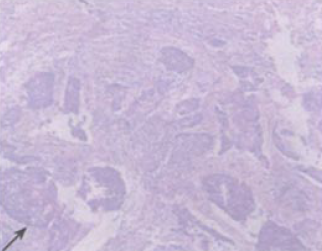

诊断:卵巢肿瘤?子宫肿物? 治疗:行行剖腹探查术。术中发现腹腔内淡黄色腹水约250ml,子宫增大如孕80余天,右侧宫角处明显突出,质地硬,左侧卵巢表面长出一菜花状结节12cm×10cm×10cm,无包膜,粘连于子宫后方,左侧盆腹膜后有一巨大包块向腹腔及右侧延伸,肝、胃、肠、大网膜无异常,盆腔淋巴结肿大,阑尾与肠系膜粘连。行腹膜后肿瘤切除及全子宫、双附件切除术,高位结扎双侧卵巢动静脉,俞腔淋巴结取样,切除大网膜及阑尾。手术困难,术后身体恢复良好。 术后肿物病理诊断提示:(1)(腹膜后肿物)脂肪瘤样脂肪肉瘤。(2)(左侧卵巢)浆液性乳头状腺癌。(3)(子宫肿瘤):子宫低分化腺癌,伴鳞状上皮分化,宫颈及部分卵巢未见肿瘤。